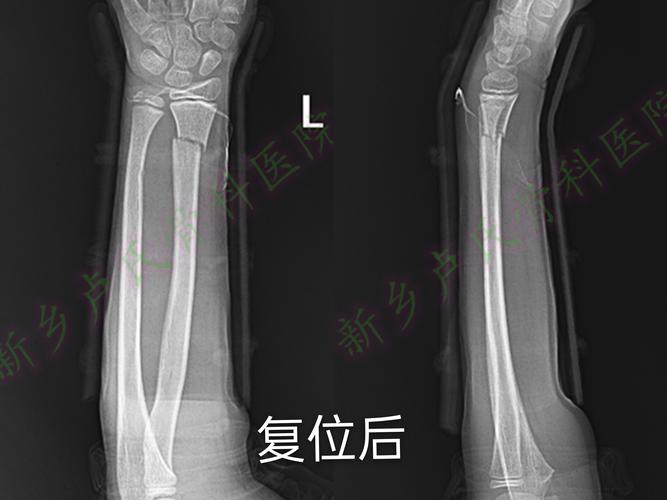

儿童尺桡骨远端骨折

桡骨远端骨折手法复位及康复注意事项

桡骨远端骨折手法复位

桡骨远端骨折复位图片